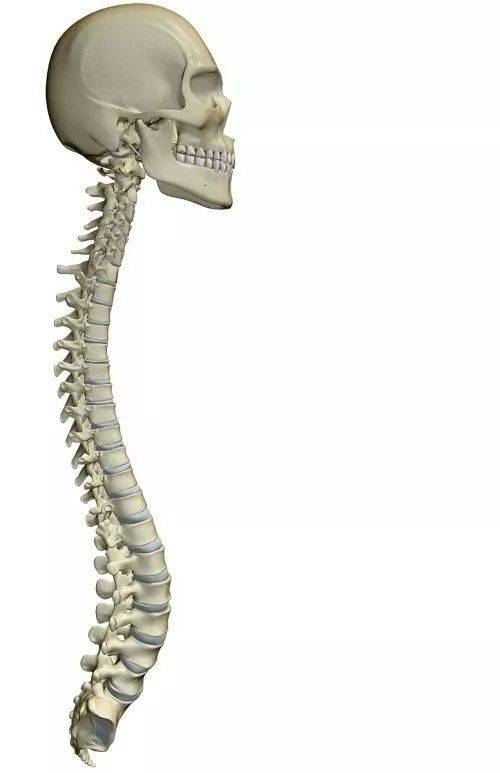

凸起 c2椎棘突 c7最高 与肩胛冈内缘平行 肩胛下角水平 隆椎 t3棘突 t

在临床触摸检查时,多以c2,c7,t3,t7,t11,l4的棘突来定位,再依此推算

矢状面角度:t1:25度;t2:20度;t3:15度;t4-9:10度;t10:5度;t11-12:0度